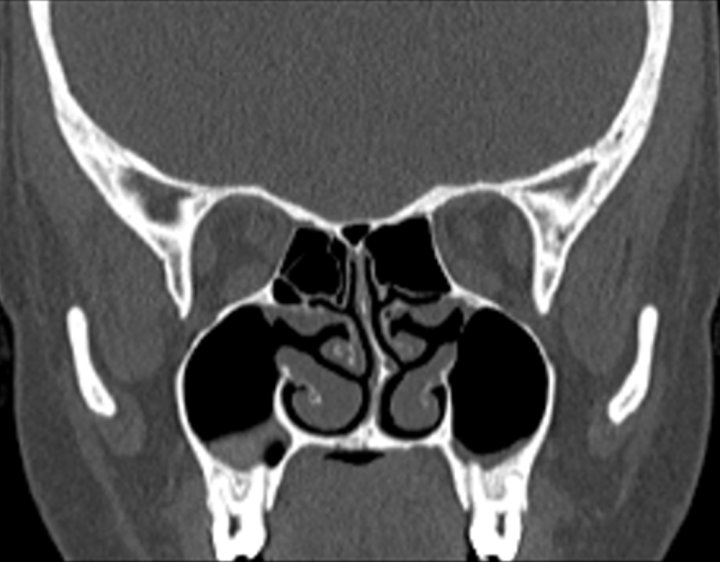

Click any image for labels.